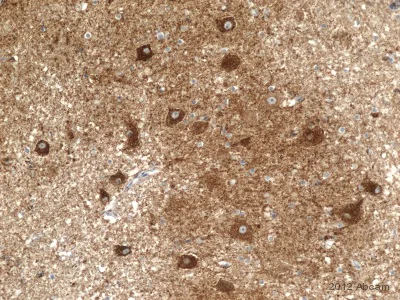

Immunohistochemistry (Formalin/PFA-fixed paraffin-embedded sections) - Anti-NDUFB4 antibody [17G3D9E12] (AB110243)

Immunohistochemistical detection of Anti-NDUFB4 antibody [17G3D9E12] (ab110243; 1/100, incubated for 1hr) on formaldehyde fixed human cerebellum sections. Antigen retrieval step : Heat mediated. Permeabilization : No. ab110243 was used to investigate respiratory deficiency in 5µm cut sections of FFPE human cerebellum. Sections were cut and mounted on to glass adhesion slides for staining. The antibody stained specifically, identifying both normal neurons as well as those exhibiting respiratory deficiency. Non-specific background staining was not evident, and positive staining was crisp and punctate. Detection - Menarini Diagnostics X-Cell Plus HRP-Polymer Kit. SigmaFast DAB tablets were used for the final stage of staining.

This image is courtesy of Philippa Hepplewhite, University of Newcastle, UK